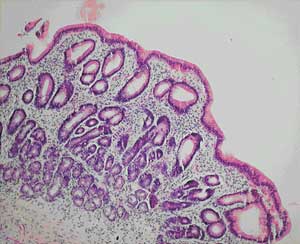

The clinical presentation, histological findings and response to tetracycline and folate therapy in our patients, seen at Cairns Base Hospital between 1998 and 2004, support a diagnosis of tropical sprue. To our knowledge, these are the first reported cases in Australia.

All of our patients were Indigenous patients living in remote Indigenous communities. The alcohol use by the first patient clouds the picture, as high alcohol intake is associated with nutritional deficiencies. However, the partial villous atrophy on biopsy is more suggestive of tropical sprue. Additionally, despite being in hospital and not drinking alcohol for 2 weeks, there was no response in his weight or biochemical test results until therapy for tropical sprue commenced. Finally, his weight gain and improvement in biochemical test parameters continued despite ongoing alcohol misuse on discharge.

The absence of an agreed definition for tropical sprue has created difficulties. It has been noted that many asymptomatic people living in the tropics will have subclinical malabsorption and even abnormal small bowel biopsy results when rigorously assessed. Uncertainty in the diagnosis of tropical sprue is compounded by the condition’s incompletely understood aetiology. It is proposed that gastrointestinal infections, which occur at a higher rate in the tropics, cause mucosal injury and initiate the process. The mucosal injury leads to a disturbance in intestinal motility, allowing the overgrowth of coliform bacteria in the small bowel.1,2 Enterotoxins from these bacteria potentiate the mucosal damage which leads to malabsorption and protein loss. The resulting nutritional deficiencies hinder epithelial recovery, and a vicious circle develops. Alteration in the intestinal microflora may also lead to a change in toll-like receptor signalling and further retardation of intestinal healing.3

A number of studies of chronic diarrhoea in Indigenous Australian children have documented partial villous atrophy on small bowel biopsy.6,7 Higher colony counts and more frequent isolation of gram-negative organisms are found in duodenal aspirates from Indigenous children with chronic diarrhoea.8 Some of these studies noted a similarity with contemporary Indian studies of tropical sprue, but therapy with antibiotics and folate does not seem to have been considered in the Indigenous children.

Our anatomical pathology service believes that small-bowel biopsies from Indigenous patients from remote communities do show a subtle increase in inflammatory cells (Dr M Jagusch, Anatomical Pathology Department, Cairns Base Hospital, personal communication), perhaps representing the subclinical tropical enteropathy described above. The relatively high incidence of gastrointestinal infections in these Indigenous communities may explain these histological findings and, by initiating the pathological process, may predispose these populations to tropical sprue.